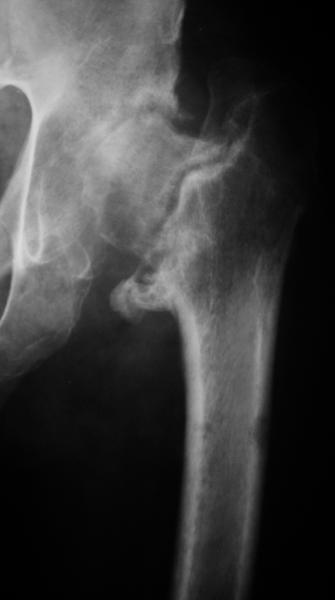

Насчет 8 см согласен с А.Н. Челноковым, это наверное ортопедическое за счет приводящей, сгибательной контрактуры и, возможно, колена. на ликвидацию укорочения у нас обычно уходит около 2-х нед. снимки в приложении, возможно не очень показательные, но других с ходу не нашел, завтра еще поищу.

Еще пара фото, ситуация несколько иная, задачи те же, открытое вправление застарелого вывиха в 2002, молодой возраст. Сейчас госпитализирована для эндопротезирования.

А за счет чего такое укорочение? По снимку не видно соответствующего дефекта. Ну плюс приводящая контрактура - но все равно как-то уж больно много. Может, сделать снимки и таза обзорный с обоими проксимальными отделами бедра, и коенный суставов с приложенной линейкой какой?

Судя по снимку, максимум истинное укорочение около 4 см, что может быть коррегировано интраоперационно. Вопрос в другом: куда ставить ацетабулярный компонент в истинную или во вновь сформированную ( впадина диспластичная).

По рентгенограммам укорочение не более 4 см, остальное возможно за счет контрактуры. Опыта с низведением аппаратом Илизарова нет, но мы одномоментно такие укорочения корригировали вполне успешно (в год 5-10 именно таких и проходит). Лишние этапы пожалуй только будут способствовать инфекции. Доступ чаше применяем передне-наружный, а вот протез наверное поставили бы здесь на цементе - остеопороз выражен.

The X ray that you provided does not show 8 cm of shortening. Perhaps you could send one showing the whole pelvis and proximal femurs.

I agree with Dr Eid's comments. The origin of the 8 cm leg length difference is a puzzle. Is this a clinical measurement? In that case contracture of the joint might affect the measurement. Can we see an AP pelvis to include both hip joints (including a calibration object with a known length) so that the difference in leg lengths that can be ascribed to the hip deformity and bony reabsorption can be measured. This sort of xray will help with templating for the TJR also. I would be very tempted to do a one stage procedure and accept some shortening. Shoe lifts should take care of a 3-4 cm difference.

До травмы проблем с ногой не было. Укорочения, болей и т.п. не отмечал. Сегодня перемерял укорочение - меньше 7 см намерять не

По уровню малых вертелов (с учетом рентгеновского увеличения) получается 5 см. Клинически ногу низвести путем тракции невозможно. Из движений - сгибание до 40*, остальные движения "символические".

Ортопедическое укорочение пострадавшей ноги может быть и 7, и 10 см. за счет контрактур в тазобедренном суставе, а вот истинное укорочение, судя по представленным рентгенограммам, вряд ли больше 4 см.

Больного прооперировали на прошлой неделе (цементный протез, цемент с гентамицином). Использовали задне-боковой доступ. В области перелома подвижности практически не было, так что тему сообщения уместно заменить на "неправильно сросшаяся шейка". И в головке, и во впадине

были значительные дегенеративные изменения, так что ни биполяр, ни остеосинтез тут неуместны (хотя это предлагали в ortopod'е). После релиза удлинили ногу на 3 см. Дальше удлинять побоялись из-за

натяжения седалищного нерва, хотя в принципе можно было бы еще 15-20 мм нарастить. По послеоперационной рентгенограмме анатомическое укорочение порядка 15 мм. Клинически при ходьбе - 4 см, но это за счет перекоса таза.

The patient underwent cemented THR on last week. Postero-lateral approach was used. There was only minimal motion at the fracture site and we had to cut the femoral head with oscillating saw. The femoral head was deformed with it's cartilage completely absent in some areas.

Acetabulum showed gross degenerative changes, especially in superior rim. So I think it was right choice not to do ORIF in this case. After some soft tissue release we've lengthened the leg up to 3 cm. Further lengthening was possible but we stopped at that moment due to tension of n. ischiadicus. Now patient walks with crutches. Leg length discrepancy is about 4 cm due to pelvic tilt (discrepancy on post-op x-ray is 15 mm).